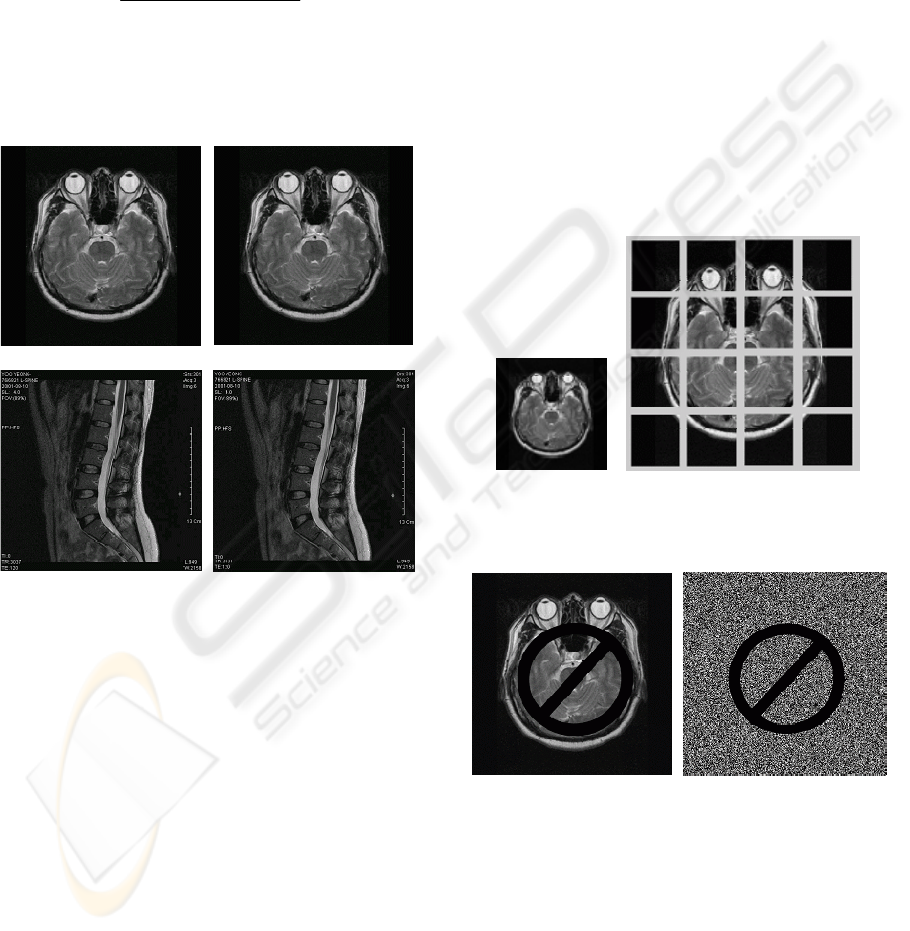

3 EXPERIMENTAL RESULTS

Computer simulations were carried out to

demonstrate the performance of the proposed

watermarking method. Performance of the PC is

Pentium4 CPU 3GHz, 512MBRAM. We changed

the stored files to common image data through the

program VisualGate, which is offered on

http://www.infinitt.com/ and stores image files with

the form of DICOM. To estimate subject

performance of invisibility, we generated many

watermark-embedded images through various

algorithms. The PSNR (peak signal-to-noise ratio)

was used as an objective measure. The NC

(normalized correlation), shown in Eq. (8), was used